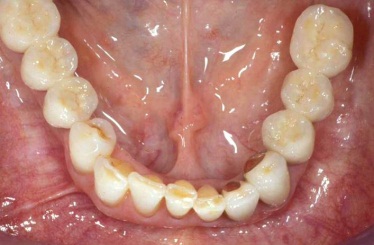

Protetické řešení může být pomocí můstku, který je kotvený na implantátech nebo pomocí jednotlivých korunek na implantátech.

V zásadě je možné do těchto můstků zařadit i přirozené zuby, zejména pokud je potřeba tyto zuby ošetřit proteticky – korunkami. Korunky nebo můstky mohou být na implantáty nacementovány nebo přišroubovány.

Zdravé zuby zůstanou zachovány a přitom náhrady jsou pevné, jako na vlastních zubech